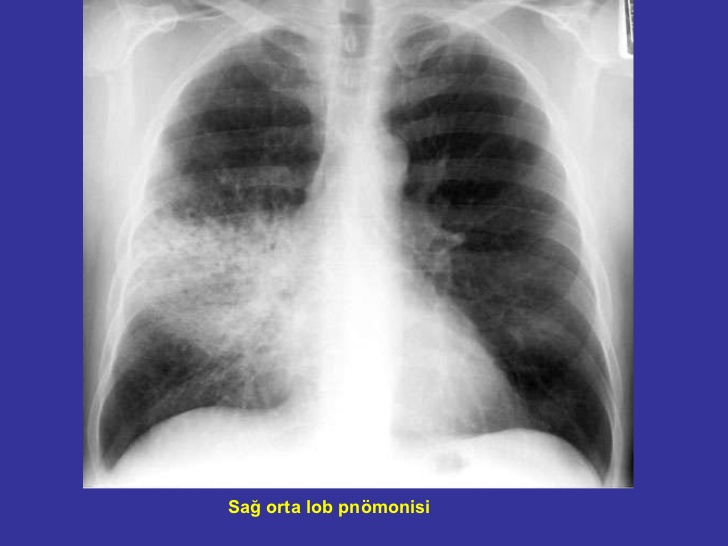

Gözünüzde bulunan kılcal damarların kanamasına neden olabilmektedir. Akciğerde kılcal damar kanaması. Kanaması her zaman sabit bir akış anlamına gelmez. Lasonil gibi merhemler daha çabuk.